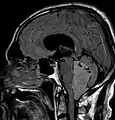

Les épendymomes supratentoriels (SE) représentent entre 40% et 60% des tumeurs intracrâniennes. Localisées au niveau supratentoriel, ces tumeurs apparaissent comme des grosseurs peu homogènes, présentant des zones kystiques, des calcifications mais également des zones hémorragiques et nécrosées.

Aspect radiologique à l’IRM en séquence T1 après injection de Gadolinium d’un épendymome supratentoriel, caractérisé par une lésion bien délimitée du lobe frontal gauche avec prise de contraste hétérogène et des zones de nécrose.